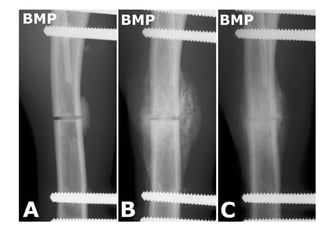

Reparación en algunos

tejidos Partículares

Hueso